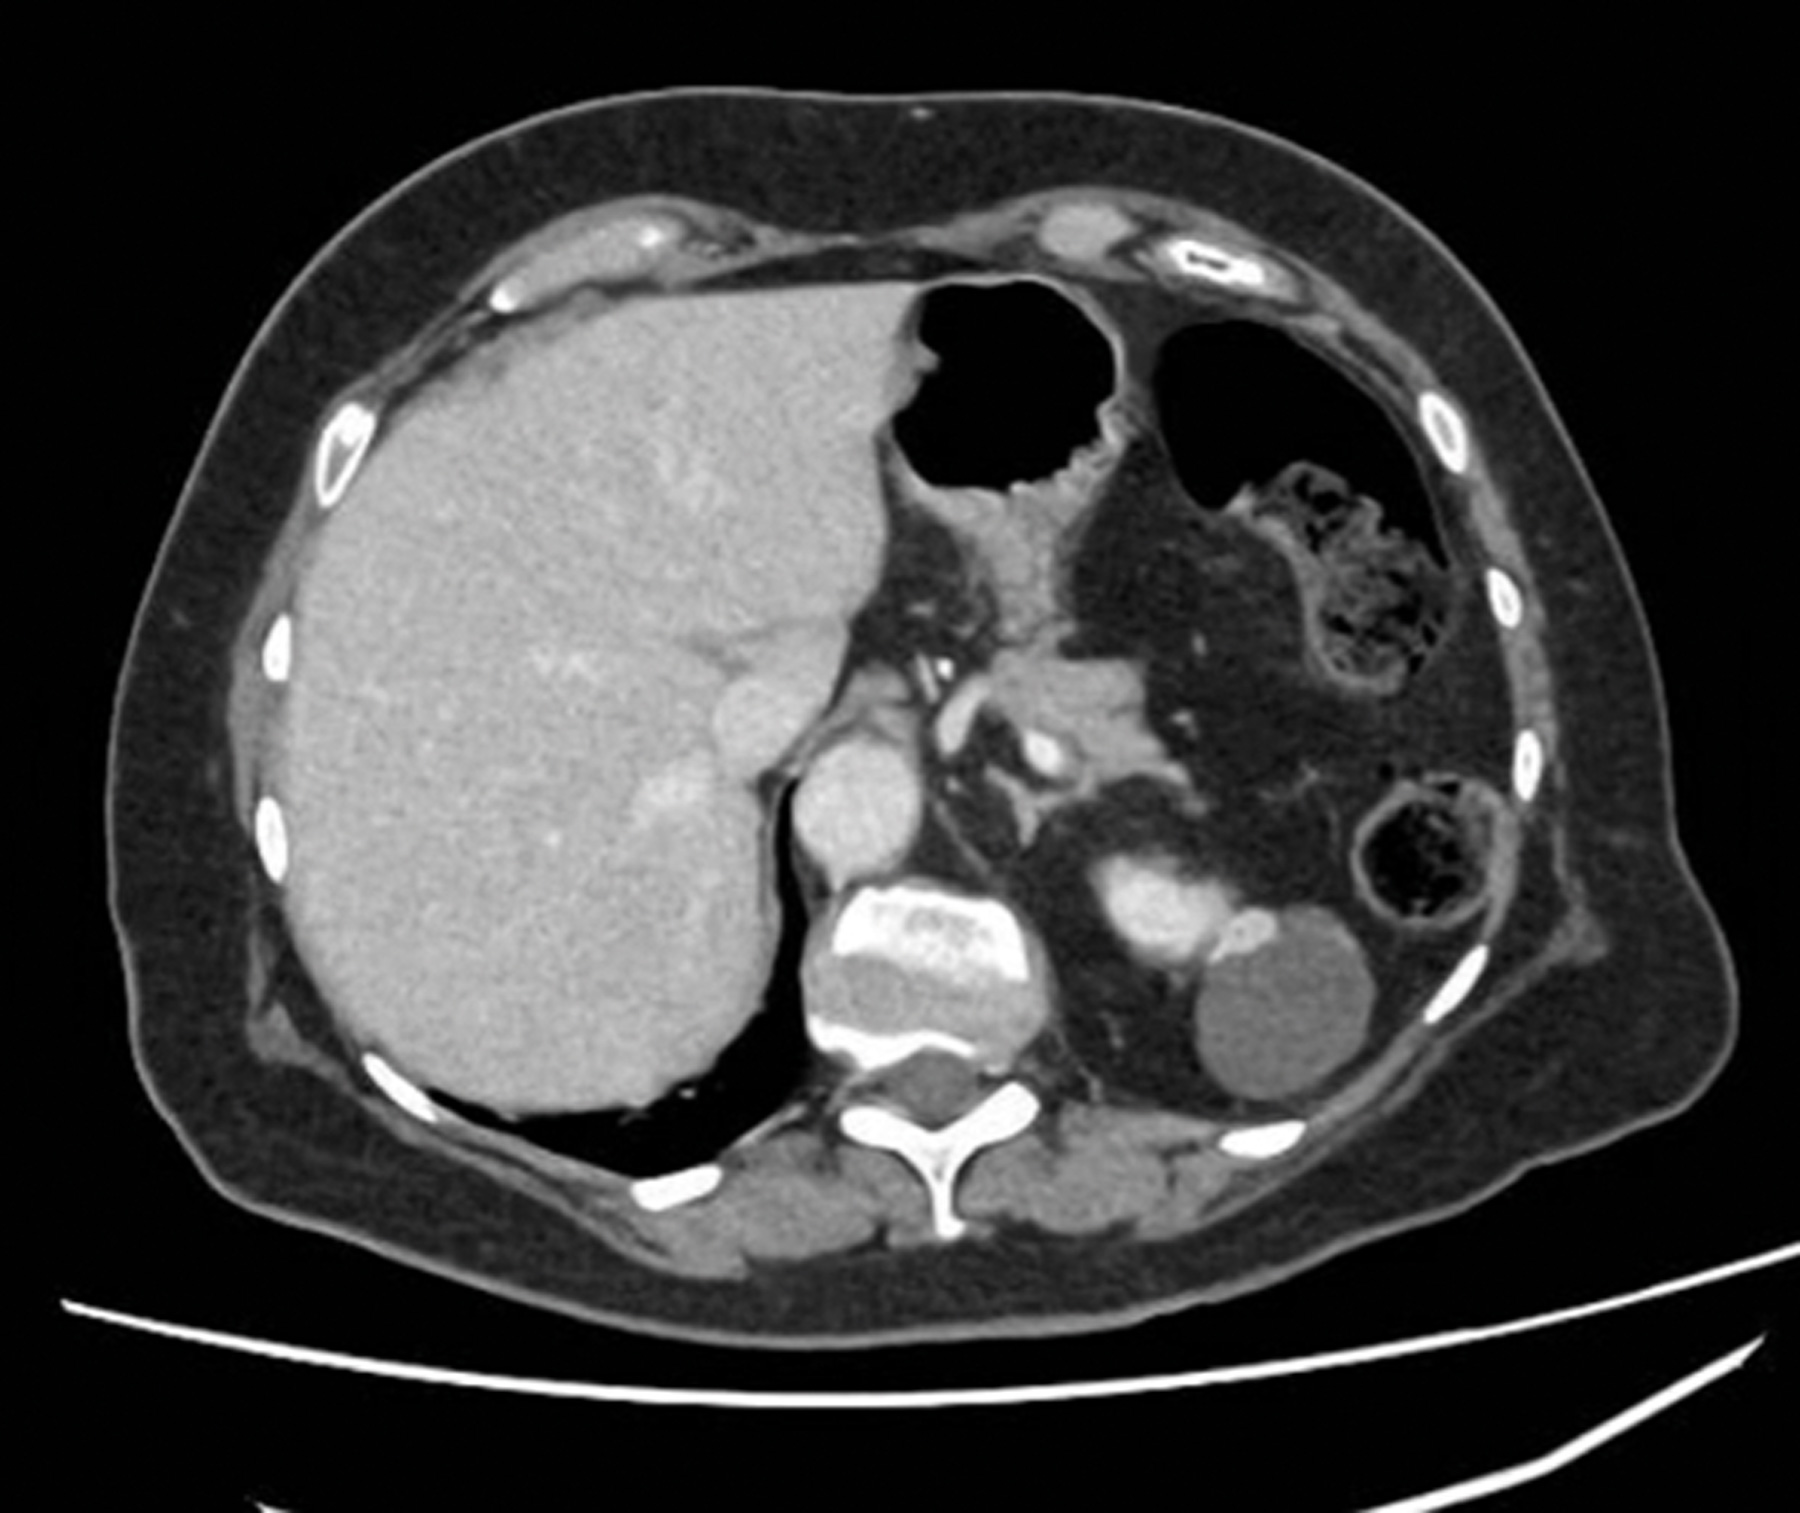

Case 2

A 65-year-old gentleman presented with visible haematuria and underwent the below CT scan. He has hypertension and hyperthyroidism.

Figure 2.

Figure 3.

1. CT renal consists of multiple phases as outlined below [8]: Non-contrast phase - This is conducted prior to intravenous (IV) contrast administration, with the purpose of detecting calcifications (e.g., renal or ureteric stones) and identifying fat content in mass lesions (e.g., AML). It is also useful in having a baseline attenuation with which to compare the contrast images.Corticomedullary phase - This is conducted approximately 25-40 seconds after contrast injection. Its purpose is to highlight renal arteries, cortex and medulla (the renal cortex enhances preferentially). It is useful in assessing vascular anatomy which can aid surgical planning, and in demonstrating renal artery stenosis / arteriovenous malformations and other abnormalities. It can identify early enhancement in hypervascular tumours.Nephrogenic phase - This is conducted approximately 80-120 seconds after contrast injection. It allows both enhancement of the cortex and medulla and is the best phase for detecting renal masses.

2. This is a 5cm, exophytic, cystic, superior pole tumour of the left kidney, stage T1b N0 Mx.